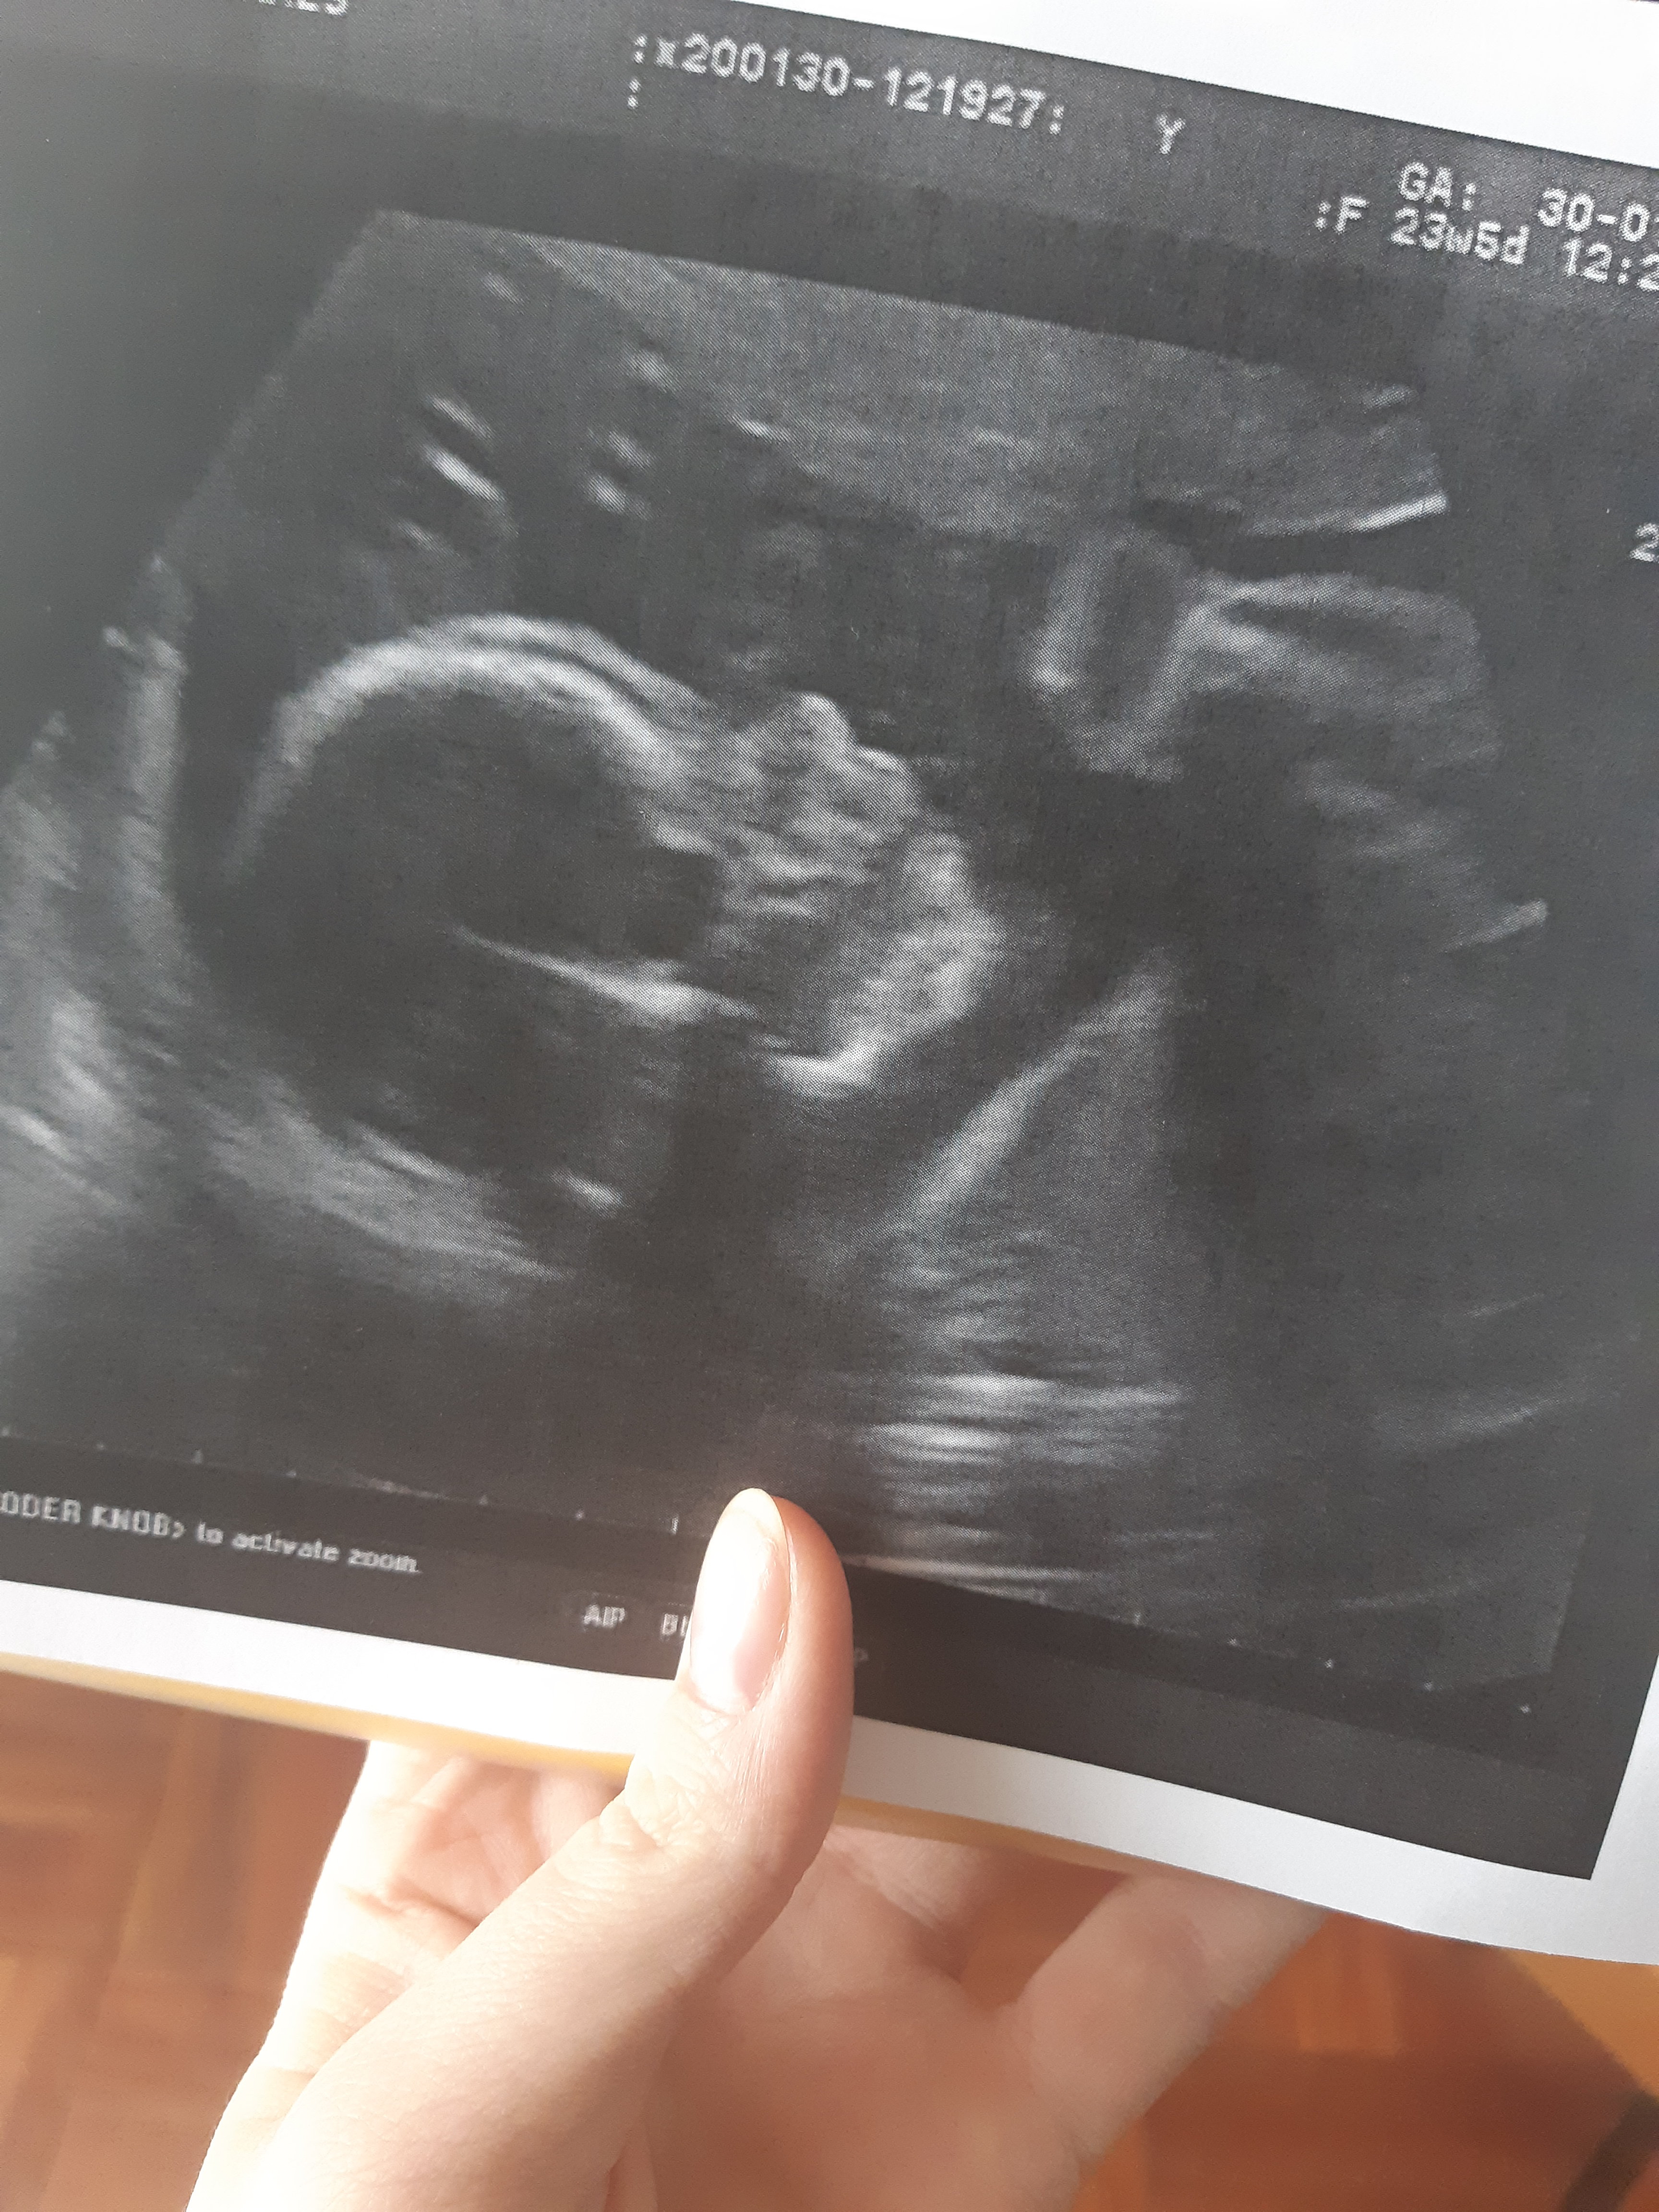

Więc my juz po, 23+5 tc, mała na tę chwile ma 622g, ciągle wystawiła język mamie i tacie . Mama wazy 65 wiec +3kg od poczatku ciazy. Na ból głowy woda , dużo wody i do dwóch tabletek paracetamolu na dobę na bóle krzyża. Na hemoroidy maść. Na bezsenność nic nie poradzi. Na pryszcze tez nic. Na skurcze i stwardnienie brzuszka podwojna dawka magnezu. Skierowanie na krew i glukoze na za tydzień. Kolejna wizyta za 3 tyg z wynikami.

• 20200130_123313.jpg

20200130_123313.jpg

2,1 MB · Wyświetleń: 115

Cudowna Malutka. Bardzo fajne zdjecie. Też liczę na to że będę dzisiaj mieć. U mnie dzisiaj 26t1d.